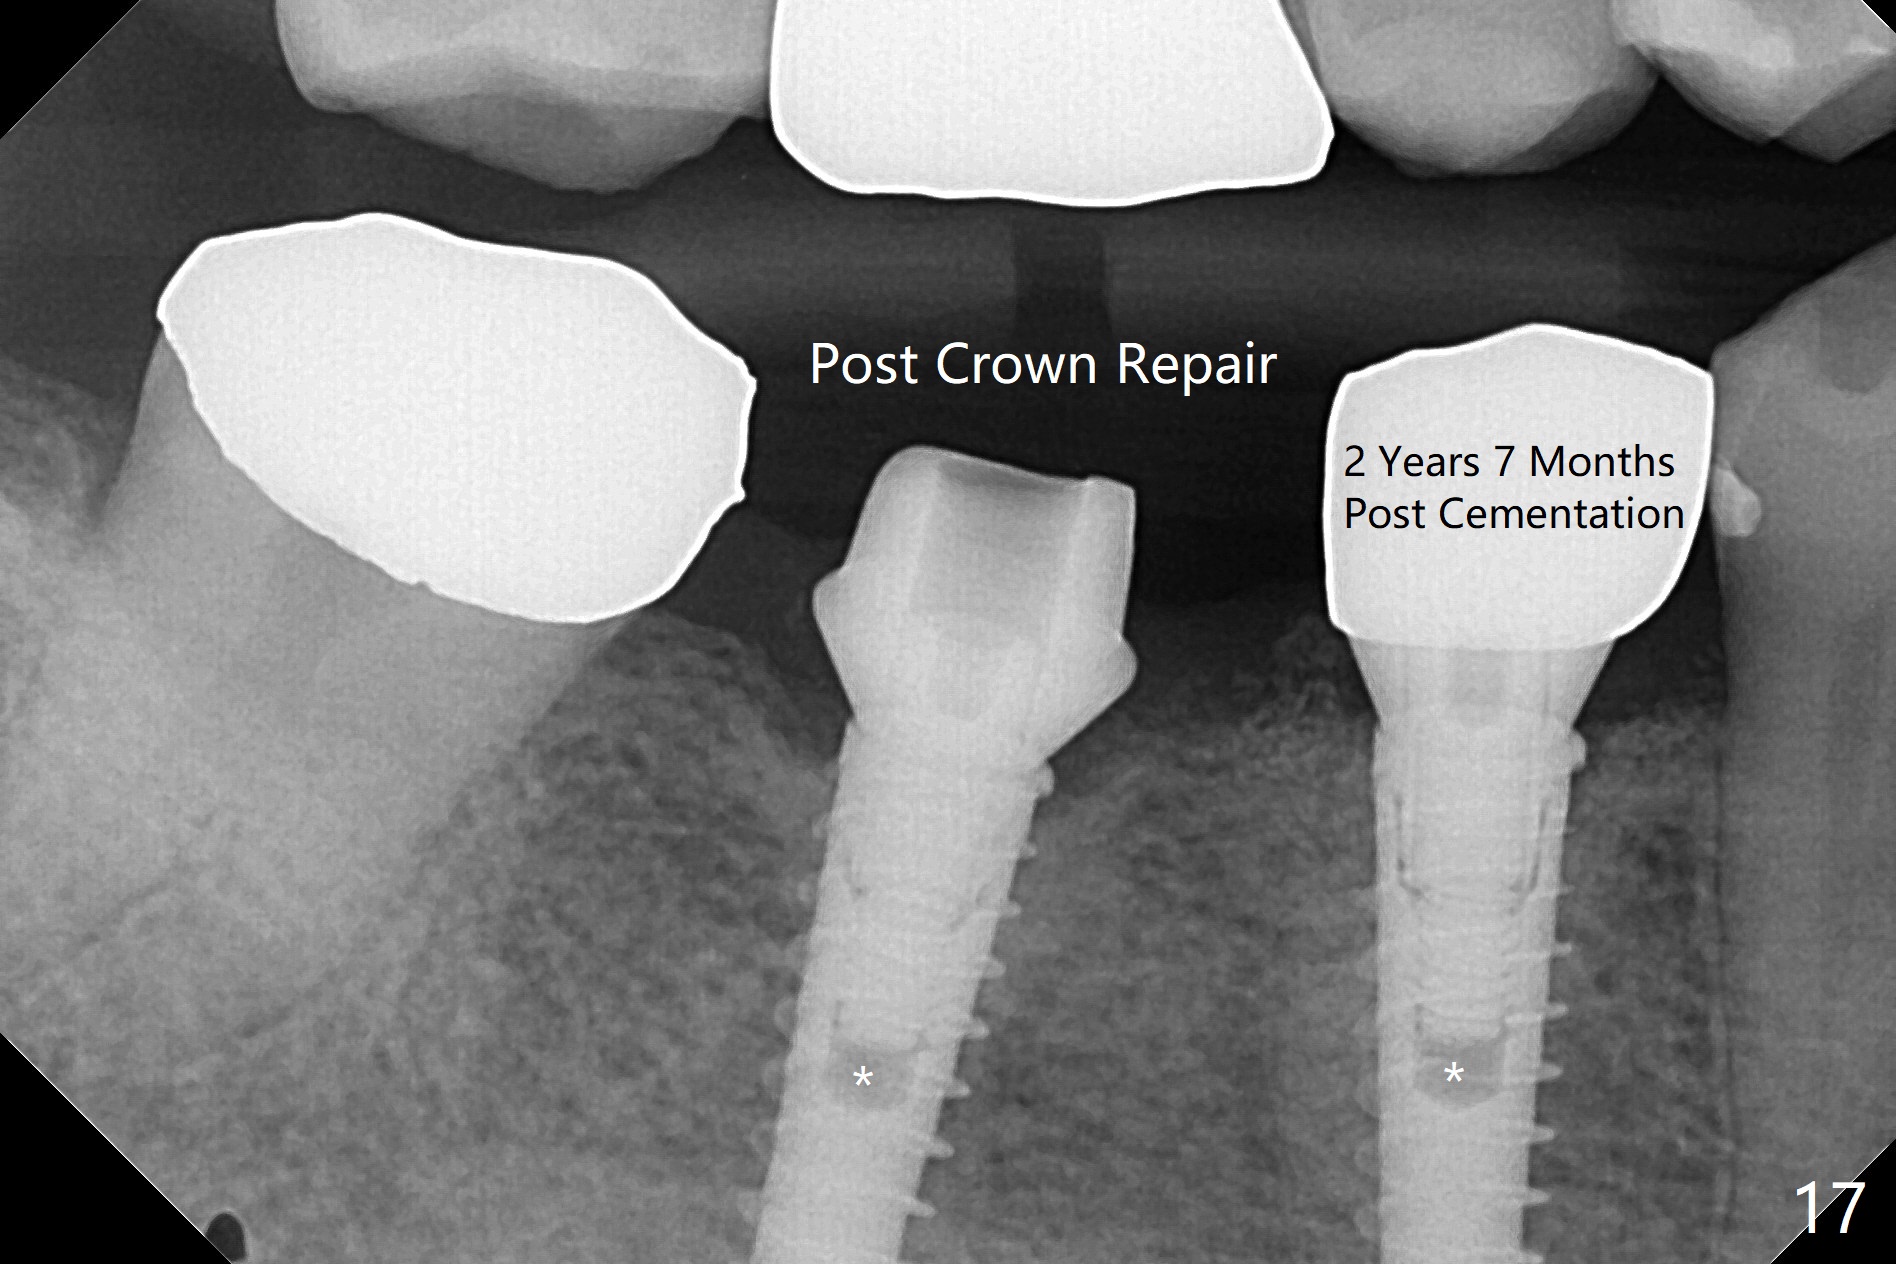

BEB for Narrow Molar Ridge

After incision, the ridge at #29 and 30 is found ~ 5 mm wide buccolingually. To place a 4x11 mm IBS implant at #30, the ridge is expanded using BEB technique (bone expansion and bending, Fig.1). It appears that the initial osteotomy at #29 is mesial (Fig.1 yellow dashed line: the distal surface of the root of the tooth #28). After moving the osteotomy distal, the final implant position at #29 (4x11 mm) is within normal limit (Fig.2). The bone at #29 seems to be not so dense that bending (using 1.6 mm drill) is not necessary (using Magic Split and Magic Expanders 3 and 3.8 mm). Later the implant at #30 (4x11 mm) is placed deeper (Fig.3). After placing bone graft around the implants/abutments and suturing, the ridge looks wider with apparent formation of the gingival bands around the abutments (Fig.4 *). Three months and a half postop, bone loss is minimal (Fig.5) and gingival bands forms around the abutments (Fig.6). Fig.7 is taken 1 month post cementation (panoramic X-ray). The patient chews normally 1 year (Fig.8) and nearly 2 years (Fig.9,10) post cementation. The crown at #31 needs recementation 2 years 7 months post #30 cementation; the incomplete seating of the abutment was noted for the first time (Fig.11). Five months later the patient is going to be retired and wants to travel abroad. After approval, the access hole was reopened; articulating paper shows under occlusion of the crown (Fig.12). Since the gap between the abutment and the implant is large, the abutment/crown complex seems to be necessary to be turned (Fig.13 curved arrow). The proximal surfaces of the crown need to be trimmed (straight lines). After turning, the crown sits down with screw tightening; the patient feels pain from the gingival cuff (Fig.14). After turning, the abutment appears to be completely seated (Fig.15). In fact the mesial and distal surfaces of the crown should have clearance from the neighboring teeth (Fig.14) so that pick-up impression is able to hold the crown/abutment complex securely (Fig.16: *). The crown is separated from the abutment after crown repair. They are seated together (loose connection) using the crown as a guide to seat the abutment. BW is taken without the crown. It appears that the abutment remains seated completely (Fig.17). The apical space is equal between #29 and 30 (Fig.17, as compared to Fig.5).